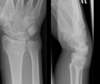

**Colles - ‘dinner fork type deformity’** Features of the injury 1. Transverse fracture of the radius 2. 1 inch proximal to the radio-carpal joint 3. Dorsal displacement and angulation of the distal radius

**Smith's fracture (reverse Colles' fracture)** 1. Volar angulation of distal radius fragment (Garden spade deformity) 2. Caused by falling backwards onto the palm of an outstretched hand or falling with wrists flexed